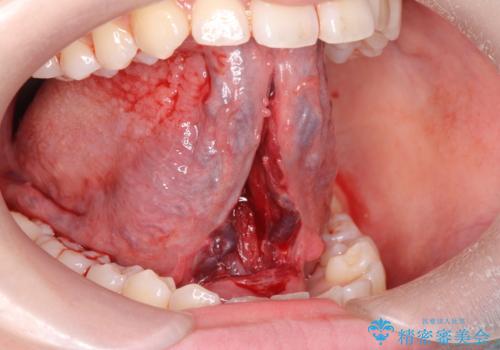

- ら行が言いにくいとの事で来院。舌の動きを舌小帯が邪魔していたので舌小帯の形成術を行いました。

舌小帯の形成手術を行うことにより舌が口蓋に届くようになり

ら行が言いやすくなりました。